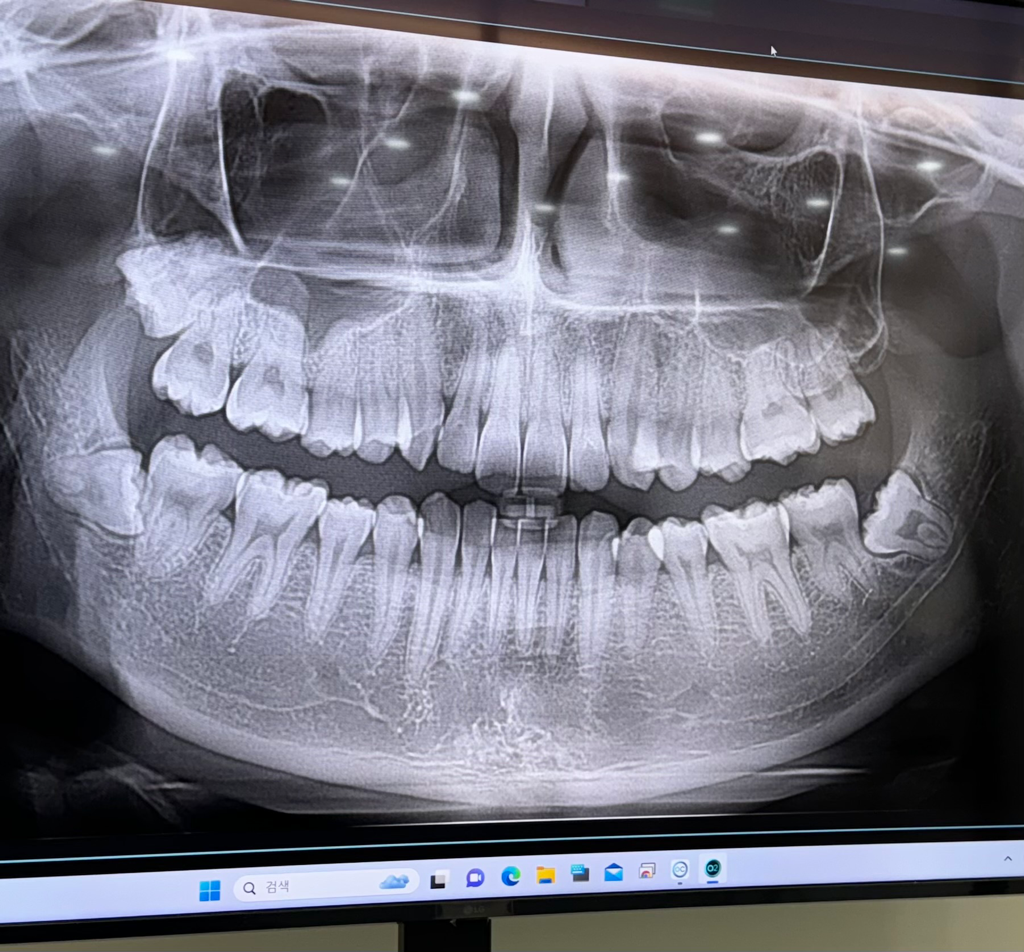

왼쪽 위아래 사랑니가 나야할 자리에 위아래로 연결된 끈 같은게 있는데 한 두달전부터 입벌릴때마다 땡기고 아픕니다. 오른쪽 아래어금니 크라운을 씌울 때 입을 계속 벌리고있었는데 그 때부터 의식하게돼서그런지 자꾸 신경쓰입니다. 사랑니가 나는 자리에도 약간 꺼끌꺼끌하게 상처같은게 나있는 것 같아요(혀로 만지면 느껴집니다.) 입을 최대한 크게 벌리면 저 끈같은게 끊어질 듯 아프고 사진도 자세히 보시면 말씀드린 끈같은것에 노란색 고른같은게 있어보입니다. 구강암같은 것일까요...? 치과에서는 별 말씀 없으셨었습니다.

1. 해당 구조는 pterygomandibular raphe라고 하며 정상 구조물입니다.

2. 오른쪽 위,아래로는 사랑니가 있고 왼쪽의 경우 아래는 사랑니가 있습니다.